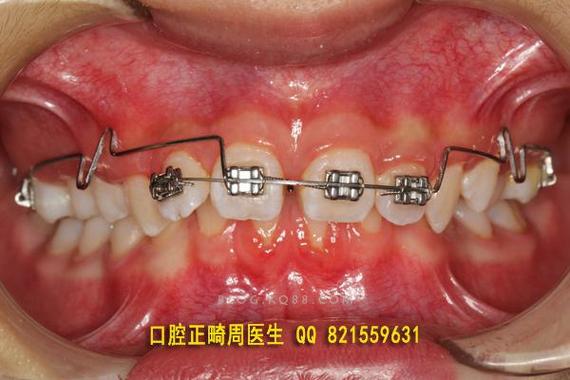

从生物力学原理看,压低辅弓通常由弹性模量较高的不锈钢丝弯制而成,通过在辅弓上设计特定曲(如垂直曲、Ω曲)与上前牙托槽或舌侧扣连接,当辅弓与主弓丝共同作用时,产生垂直向压低力及冠根向转矩控制力。“L”形辅弓的水平臂嵌入磨牙颊面管提供支抗,垂直臂与前牙托槽结扎,通过调整垂直臂高度和角度,可精确控制压低力大小和方向;辅弓的刚性形态能有效抵抗上前牙唇倾趋势,确保压低效率的同时避免牙冠过度倾斜。

制作与临床应用中,材料选择多为0.016-0.018英寸不锈钢丝,因其弹性模量高,形变后回力稳定,能提供持续的压低力,弯制时需在磨牙区预成水平臂(长度为第一磨牙颊面管至尖牙的距离),前牙区弯制垂直压低曲(曲的弧度需圆滑,避免应力集中),垂直曲顶端与上前牙托槽槽沟底保持1-2mm间隙,确保加力后产生垂直向压力,临床操作时,先将辅弓水平臂插入磨牙颊面管,再用结扎丝将垂直曲与上前牙托槽紧密结扎,辅弓与主弓丝(通常为0.019×0.025英寸不锈钢丝)共同构成力学系统,主弓丝提供支抗,防止后牙伸长,加力周期为4-6周复诊一次,每次调整垂直曲高度0.5-1mm,直至上前牙达到目标位置(如牙冠长度缩短1-2mm,覆合改善II度)。